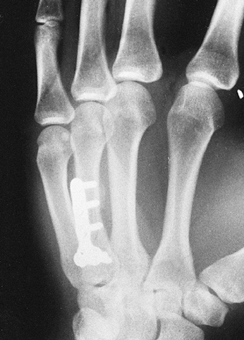

![]() |

|

Figure 40.5.

A 24-year-old laborer’s dominant right hand was crushed by a dumpster. There was extensive soft-tissue trauma associated with three metcarpal shaft fractures. A,B: Anteroposterior and oblique views revealed transverse metacarpal shaft fractures. C: Through two longitudinal incisions, one-quarter tubular plates and 2.7-mm screws were applied. D,E: Full flexion and extension were achieved within 6 weeks despite the extensive soft-tissue crush. F,G: Anteroposterior and oblique radiographs 6 months after plate removal. |